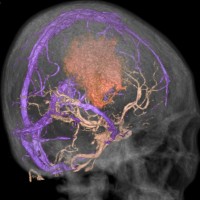

上矢状洞髄膜腫 superior sagittal sinus meningioma

上矢状洞を埋め尽くすように増大して,頭蓋骨浸潤が著しい髄膜腫ですが,ごく軽度の右足脱力以外に何の症状もありません。上矢状洞はゆっくり閉塞すれば,このような頭頂部から後頭部にわたる広範閉塞でも,静脈還流に障害がない場合が多いといえます。大脳の前半部の血流は前頭葉表面の皮質静脈から海綿静脈洞に側副路を形成しています。頭蓋内圧亢進所見もなく,これらはこの髄膜腫がゆっくり増大したということを示唆しています。

手術直後の画像です。全部いっぺんに摘出するのは無理なので,まず前から80%くらいの腫瘍を摘出しました。肥厚した骨はチタンプレートで置き換えてあります。後頭部の上矢状洞内と大脳鎌に少し残りましたが,この6ヶ月後に2回目の開頭術をして全摘出しました。結果的にこの例では,上矢状洞を冠状縫合のあたりから,静脈洞交会まで壁ごと全部摘出しましたが,脳浮腫も何も生じませんでした。腫瘍の両側にある皮質静脈 cortical veinsを損傷しないことが肝要です。

右の病理像は,頭蓋骨浸潤している部分 ですが,骨破壊は良性髄膜腫に特徴的な骨内浸潤像です。この骨浸潤像は悪性像とはいえません。MIB-1は高いところで8%、低いところで3%程度です。